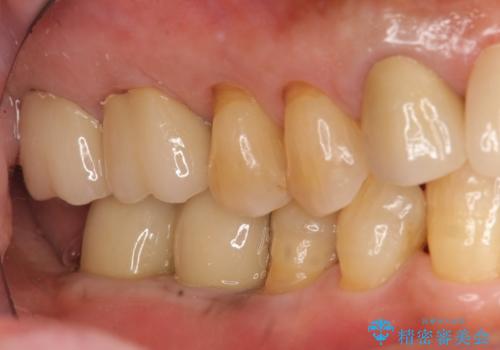

ブリッジにできない位置であったため、インプラントでかめるようにしました。

- 約250万円 右下67 インプラント2本(ストローマンインプラント20万円、カスタムアバットメント10万円、シリンダーTeC 2万円 以上2本、マイナーGBR5万円) 再根管治療 (前歯 9万円x1、小臼歯11万円x1 大臼歯:専門医による再治療 15万円x3本) ジルコニアクラウン(右上2367、右下I6I7、左上56 10万円x8 )仮歯 1万円x8本 ファイバーコア 2万円x5 セラミックインレー(左上5) 7万円x1 フラットタイプナイトガード 3万円費用は治療当時の料金となります

セラミックが欠けるのを防ぐため、また、左上7は対合歯がなく挺出してしまうのを防ぐため、ナイトガードを就寝時に装着していただいています。